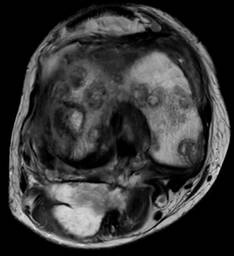

Tres meses previos a nuestro contacto, se realizó resonancia magnética (RM) con datos de proceso inflamatorio difuso sobre estructuras óseas, condrales, ligamentarias, tendinosas, musculares y cápsula articular; múltiples lesiones osteocondrales en compartimento patelofemoral, femorotibial, menisco lateral y medial; quiste de Baker (Figuras 1 y 2).

Figura 1: Resonancia magnética nuclear de rodilla derecha con datos inflamatorios difusos, múltiples lesiones osteocondrales, quiste de Baker y datos sugestivos de osteomielitis.